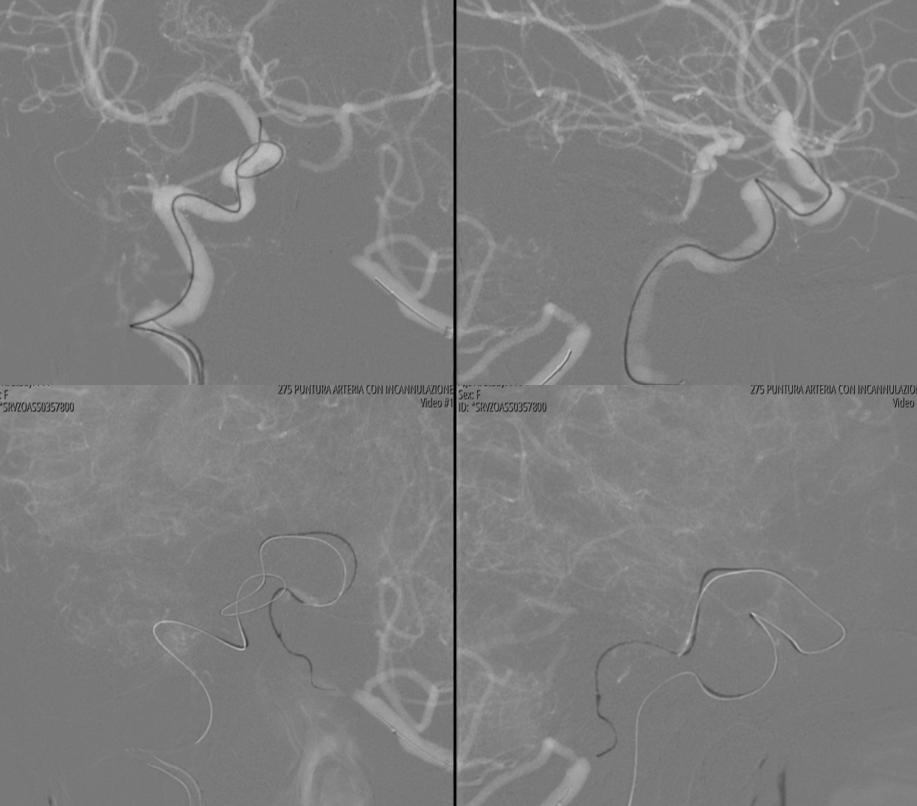

“Dry” noncontrast Vaso-CT (22 cm FOV protocol, 20 seconds acquisition, reconstructed with 50% FOV and 5123 matrix), showing the stents in the artery and the calcific plaques.

Laser-cut balloon-mounted stents make it easier to leave the PICA alone – critical given what you see below. The best choice in our opinion.

Vaso-CT (22 cm FOV protocol, 20 seconds acquisition, 50% contrast manual injection – 250 mg/ml, reconstructed with 50% FOV and 5123 matrix). We can see a stenosis at the origin of the PICA due to snowplough effect of the inflated balloon on the plaque — this is quite acceptable. With complete coverage of the PICA the result could be bad indeed. Precision matters a lot.